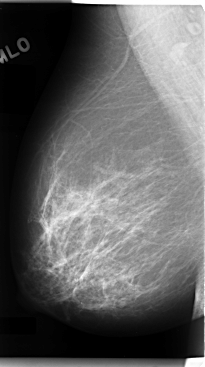

C_0089_1.RIGHT_MLO

ics_version 1.0

filename C-0089-1

DATE_OF_STUDY 16 8 1994

PATIENT_AGE 46

FILM_TYPE REGULAR

DENSITY 2

DATE_DIGITIZED 14 11 1997

DIGITIZER LUMISYS LASER

LEFT_MLO LINES 4728 PIXELS_PER_LINE 2776 BITS_PER_PIXEL 12 RESOLUTION 50 OVERLAY

RIGHT_MLO LINES 4768 PIXELS_PER_LINE 2656 BITS_PER_PIXEL 12 RESOLUTION 50 NON_OVERLAY